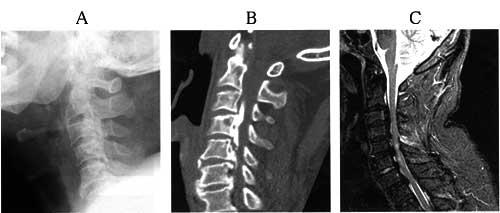

56歳の男性。階段で足を滑らせ階下まで転落し、病院に搬送された。入院時の頸椎エックス線写真(A)、CT(B)及びMRI(C)を示す。頸椎・頸髄の病変について誤っているのはどれか。

1

前縦靭帯の骨化

2

後縦靭帯の骨化

3

頸椎の脱臼骨折

4

頸髄内の損傷像

5

椎体の骨棘形成

56歳の男性。階段で足を滑らせ階下まで転落し、病院に搬送された。入院時の頸椎X線写真(A)、CT(B)及びMRI(C)を示す。徒手筋力テストによる上下肢の筋力評価の推移を表に示す。感覚鈍麻は持続しているが、2週後には排尿は自力で可能となった。受傷4週以降の治療で正しいのはどれか。